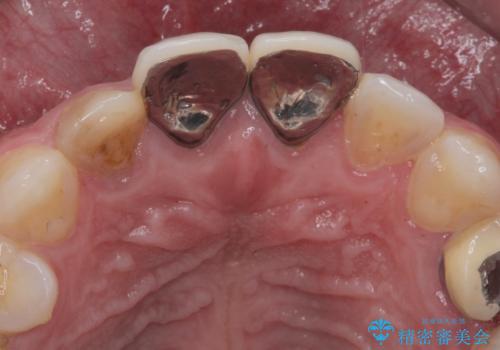

- 前歯(右上2)が黄色いとのことで来院。

レントゲンを撮ったところ前歯の被せ物が不適でした。

根管治療はご希望されなかったので(症状はなし)被せ物のやりかえ、右上2は被せ物の治療を行いました。